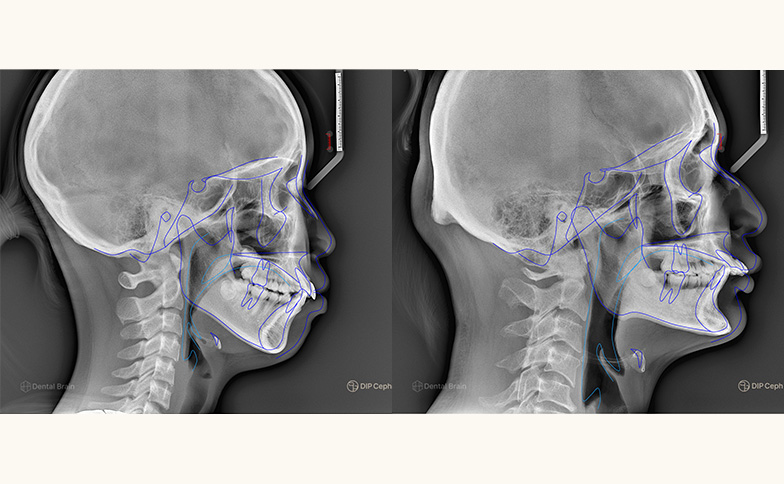

こちらの2つの症例は、どちらも「前歯の突出(出っ歯)」がお悩みで来院された患者様です。見た目は似ていますが、精密検査の結果(ポリゴン表)を見ると、その原因は全く別のものであることがわかります。

左の症例:土台となる「あごの骨」が原因

前歯の生え方に問題はありませんが、上あごの骨自体が前に出ているタイプです。この場合、骨格のバランスを考慮したアプローチが必要になります。

右の症例:歯の「生え方」が原因

あごの骨の位置は正常ですが、前歯が外側に向かって傾いて生えているタイプです。この場合は、歯の角度を内側へ整える治療がメインとなります。

このように、同じ「出っ歯」というお悩みでも、原因が「骨」にあるのか「歯」にあるのかで、最適な治療計画や装置の選択は大きく変わります。だからこそ、表面的な見た目だけで判断せず、精密な分析で「本当の原因」を突き止めることが、理想の仕上がりへの第一歩となります。